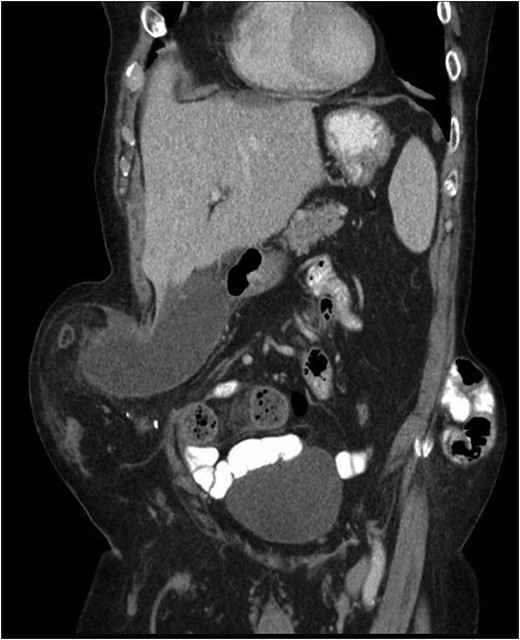

Our patient is an 89-year-old male with a history of a Hartmann’s procedure (2006) for Crohn’s disease of the sigmoid colon followed by a reversal of the colostomy with a diverting loop ileostomy (2008). Due to his comorbidities and age, the patient declined further surgery to reverse his loop ileostomy. Most recently, the patient presented to the emergency room with no ostomy output for the past 14 h, nausea and frequent burping. He reported a burning sensation around his ostomy. His physical examination revealed a large parastomal hernia in the right hemiabdomen and associated tenderness in the right upper quadrant, with no overlying skin changes. His white blood cell count was 8.1 (82.4% neutrophils), and he had normal liver function tests. A computed tomography (CT) scan of the abdomen and pelvis revealed a large parastomal hernia with a wide neck containing a distended gallbladder concerning for acute cholecystitis, as well as a small bowel obstruction with a transition point at the level of the hernia (Figs 1 and 2). A previous CT scan showed the same hernia with a nondistended gallbladder and non-obstructed bowel entering and exiting the stoma (Fig. 3).

CT from May 2017 with decompressed gallbladder and unobstructed bowel.